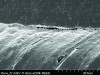

The mechanism of adhesion is similar for enamel and dentin—a micromechanical entanglement of monomers into the enamel microporosities or collagen interfibrillar spaces created by acid dissolution of mineralized tissues.45,46 When evaluating restorative success, the marginal integrity achieved by this procedure becomes a priority since an intact restorative–tooth interface is essential to the exclusion of bacteria and the interfacial hydrodynamic equilibrium of the dentino-pulpal complex (Figure 8 through Figure 11).

Figure 1. This canning electron microscope (SEM) image reveals a restorative material properly bonded to enamel and dentin that provides the potential for long-term functional success. (Courtesy of Jorge Perdigão, DMD, MS, PhD.)

Figure 1

Figure 2. This SEM view illustrates a restorative material improperly bonded to enamel and dentin that can result in clinical failure. (Courtesy of Jorge Perdigão, DMD, MS, PhD.)

Figure 2